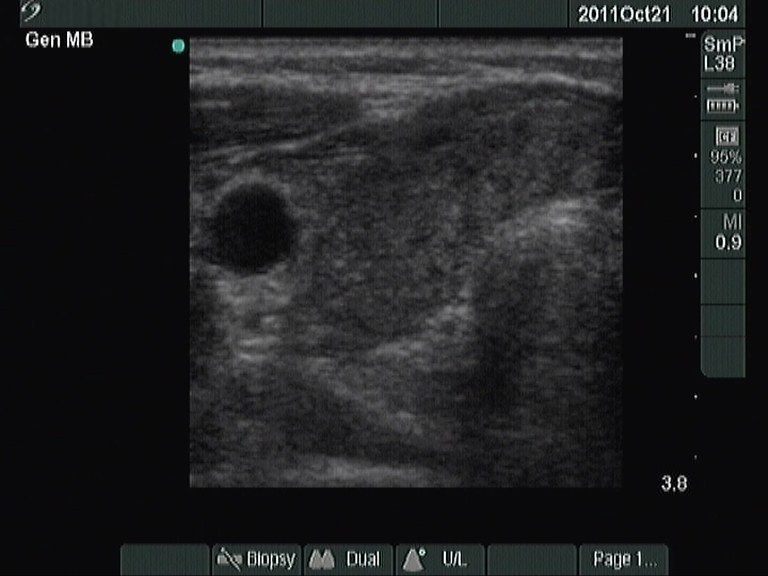

First examination (1st row of images):

Clinical presentation: a 63-year-old woman came to a yearly follow-up examination because of a known thyroid nodule and a hypothyroidism replaced with daily 75 microgram levo-tiroxine. She had neck discomfort She had neck discomfort while turning her head to the right.

Palpation : there was a nodule in the left lobe.

Hormonal investigation: indicated euthyroidism with TSH-level 1.01 mIU/L.

Ultrasonography: revealed hypoechogenic inhomogeneous thyroids. There was a hyperechogenic nodule in the left lobe. The nodule presented a halo sign and perinodular blood flow. It increased in size, therefore we performed aspiration cytology.Cytology: benign lesion.